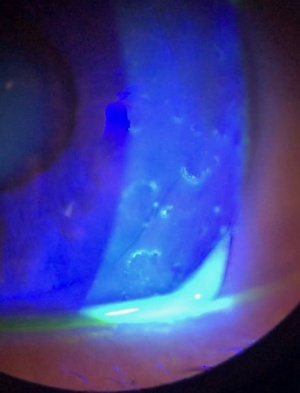

Slit lamp exam shows randomly dispersed Landolt-shaped rings in the corneal epithelium, which can be enhanced with fluorescein staining. Figure 1 is a slit lamp photo of a patient with Landolt ring-shaped lesions. The shape (i.e., the location of the gap in the “C”), number, and size of the ring lesions varied from patient to patient and from visit to visit, eventually resolving with disease remission. Vesicular changes can be seen, but there is no apparent inflammation. Some of the patients demonstrated a “fractal pattern” wherein smaller lesions were grouped to form a larger Landolt ring. No decrease in corneal sensation was observed in tested patients, and fundoscopy was unremarkable. Intraocular pressure was normal for all patients[1].